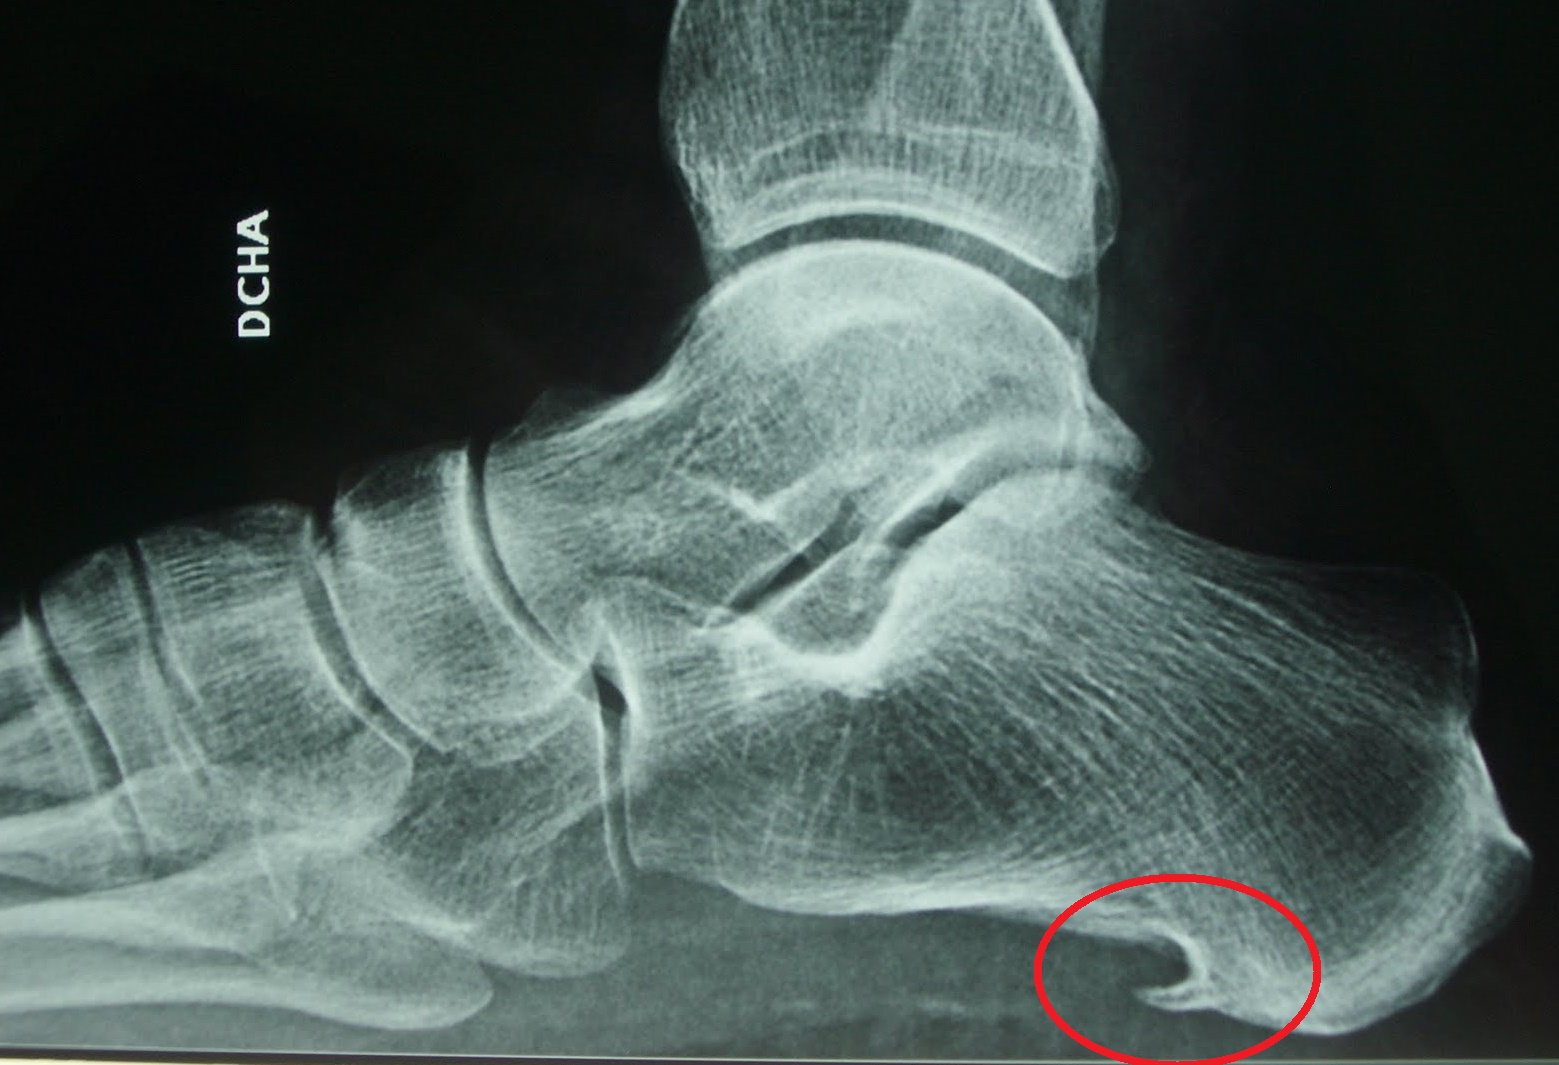

- Algunas veces, una radiografía muestra un espolón del hueso del calcaneo, a menudo se creía que estos espolones óseos eran responsables del dolor en el talón y se extirpaban quirúrgicamente. Sin embargo, muchas personas que tienen espolones óseos en los talones no tienen dolor.

- Es una prominencia ósea que se forma sobre la inserción calcánea de la fascia como respuesta a microtraumatismos repetidos e inflamación.